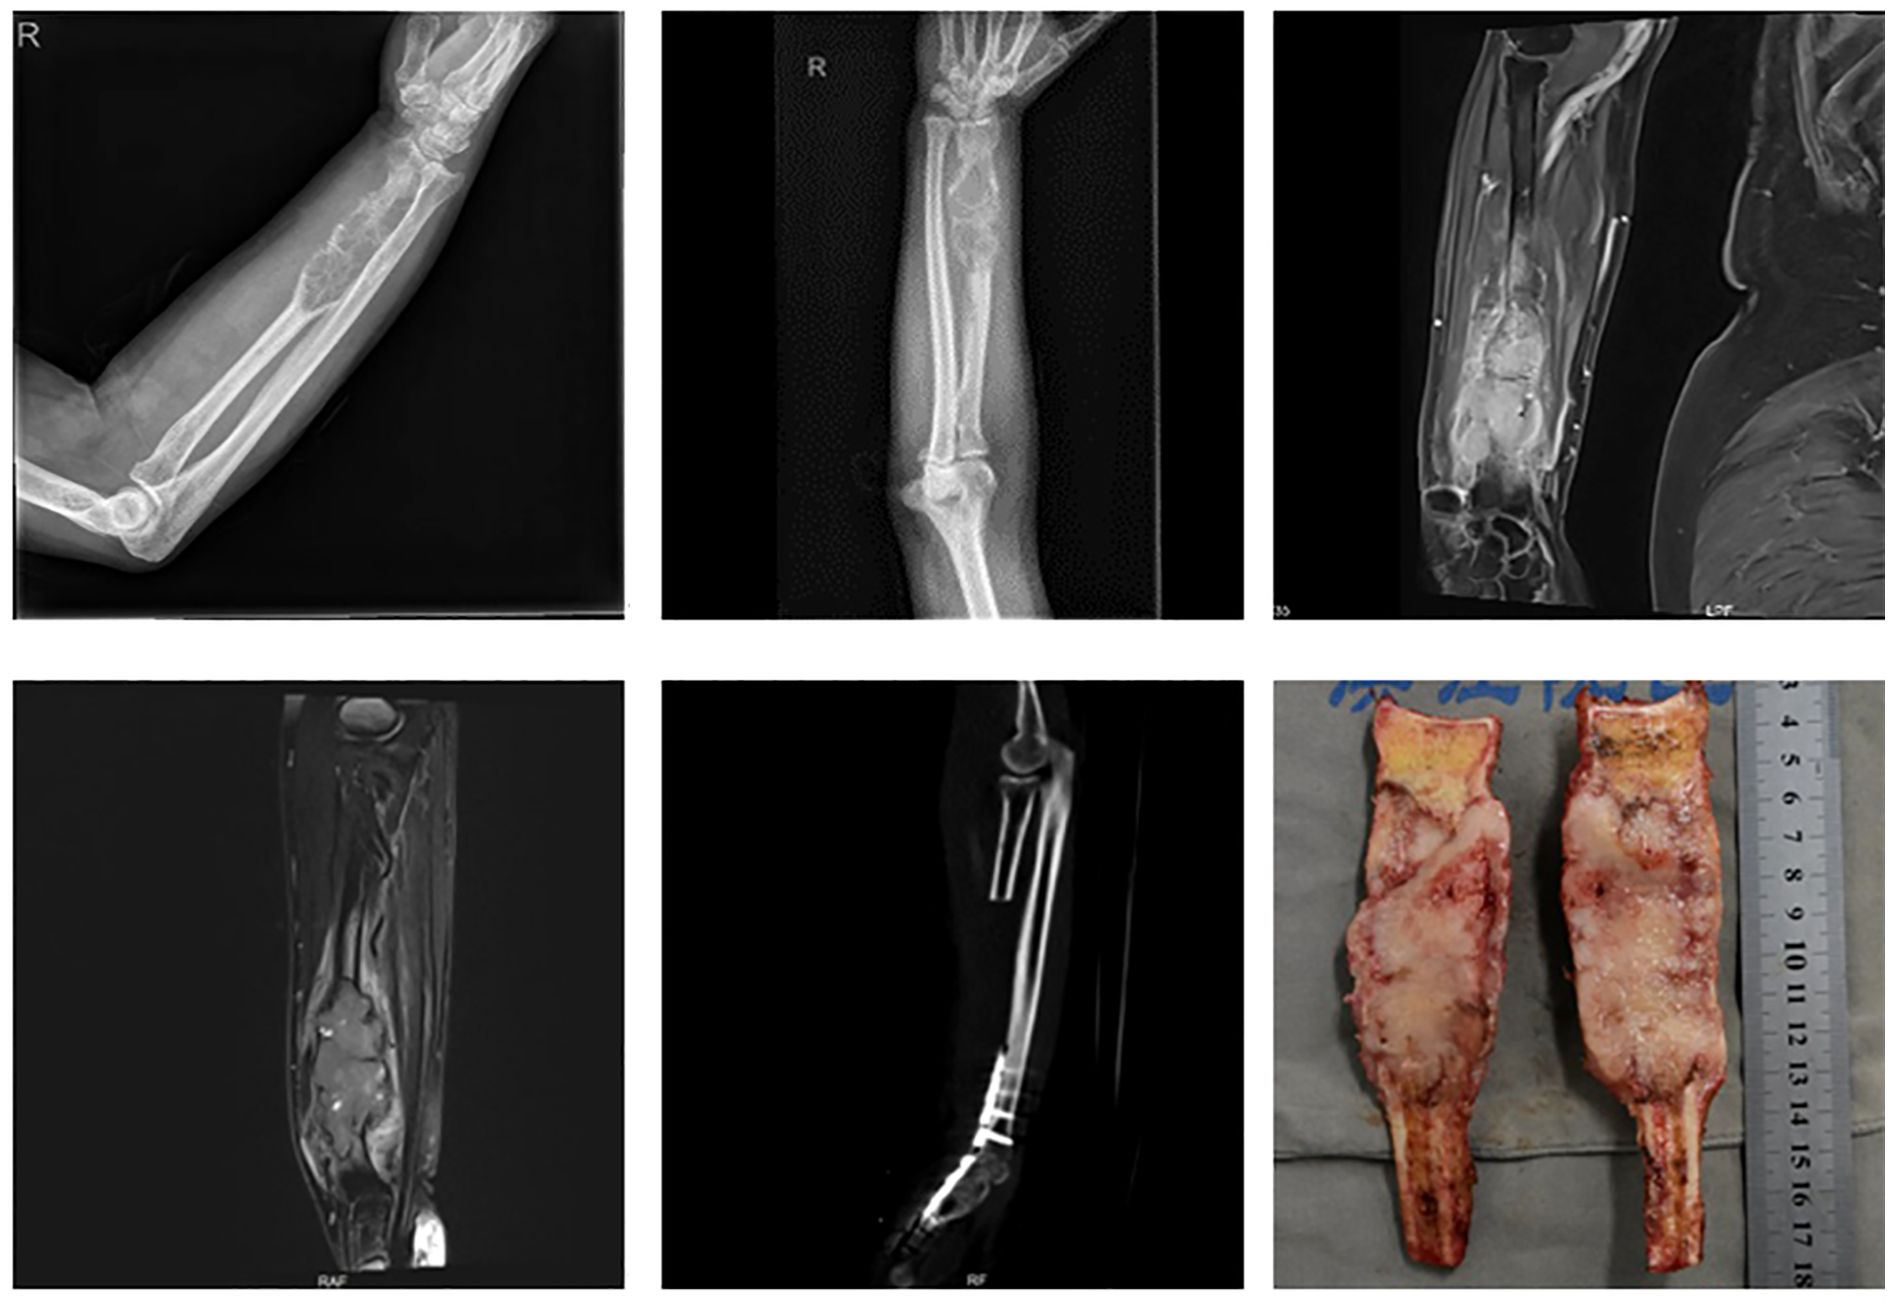

Tumors involving more than half of the distal radius (Figure 3): Reconstruction strategies included ulnar-only fixation and wrist arthrodesis.

Figure 6. A 74-year-old male with carcinosarcoma of the distal right radius involving more than half of the bone. The patient underwent large segmental resection followed by ulnar-wrist arthrodesis.

Five cases involved extended resections: one case of distal radius and distal ulna resection, one case of distal radius and proximal carpal bone resection, and three cases involving resection of the distal radius, distal ulna, and proximal carpal bones. All cases were reconstructed with wrist arthrodesis—three using autologous fibular grafts and two using ipsilateral ulnar transposition with arthrodesis (Figure 7).

Figure 7. A 46-year-old male with leiomyosarcoma of the right distal radius, with tumor involvement extending to the distal radius, proximal carpal bones, and the distal ulnar-radial joint. The patient underwent resection of the distal radius, distal ulna, and proximal carpal bones, followed by ipsilateral ulnar transposition with arthrodesis.